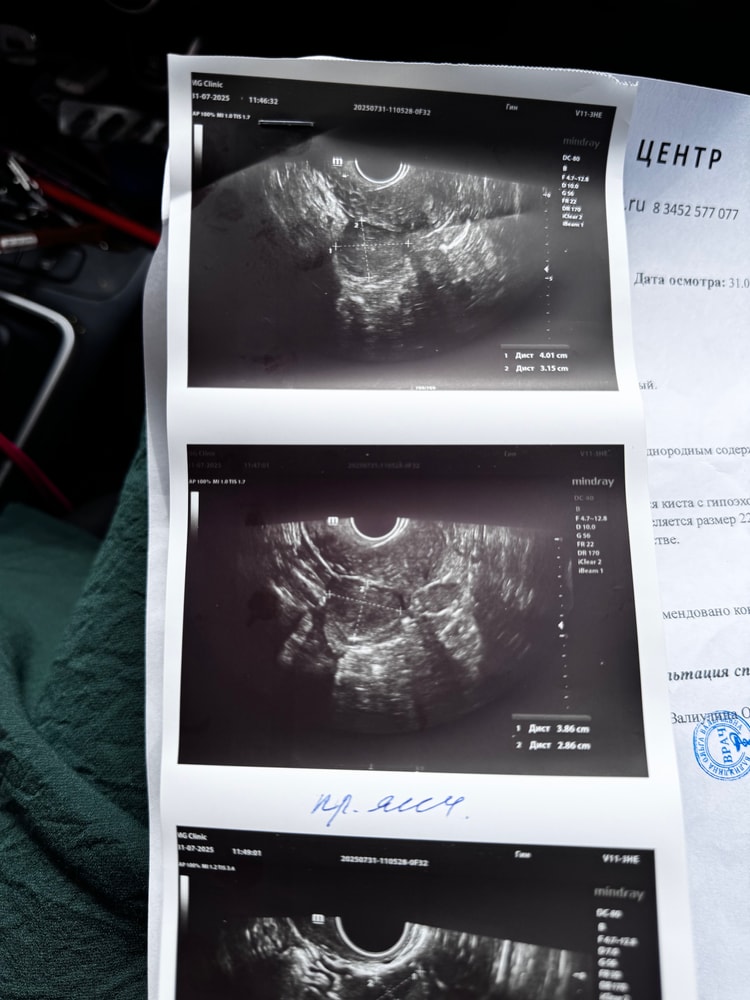

Добрый день, после укола ХГЧ 10 000 ед. сходила на узи через 6 дней, сказали киста, очень больно двигаться, почти все время колющие ощущения, девчонки миленькие подскажите это киста ЖТ или обычная, были ли у кого такие ощущения?

ниже прикрепляю узи

Скорее всего киста ЖТ, тк фолликулярная выглядит иначе